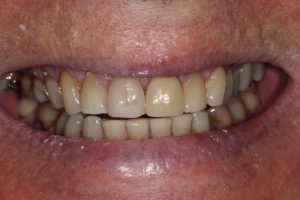

Upper Front Tooth Implant

This patient had broken their upper front tooth and the exisitng dental crown had fallen off. The underlying root was unfortunatley irreparable.

The dental root was subsequently removed and an implant placed at the same time. The implant had a temporary crown placedon the same day.

The ‘After’ photos shows the final crown that was made after 3 months. The implant crown was made to match the form and colour of the exisiting teeth to give an overall natural aesthetic finish.